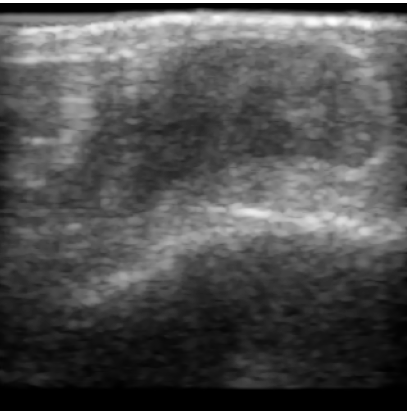

Chronic wounds including diabetic and arterial/venous insufficiency injuries have become a major burden for healthcare systems worldwide. Demographic changes suggest that wound care will play an even bigger role in the coming decades. Predicting and monitoring response to therapy in wound care is currently largely based on visual inspection with little information on the underlying tissue. Thus, there is an urgent unmet need for innovative approaches that facilitate personalized diagnostics and treatments at the point-of-care. It has been recently shown that ultrasound imaging can monitor response to therapy in wound care, but this work required onerous manual image annotations. In this study, we present initial results of a deep learning-based automatic segmentation of cross-sectional wound size in ultrasound images and identify requirements and challenges for future research on this application. Evaluation of the segmentation results underscores the potential of the proposed deep learning approach to complement non-invasive imaging with Dice scores of 0.34 (U-Net, FCN) and 0.27 (ResNet-U-Net) but also highlights the need for improving robustness further. We conclude that deep learning-supported analysis of non-invasive ultrasound images is a promising area of research to automatically extract cross-sectional wound size and depth information with potential value in monitoring response to therapy.